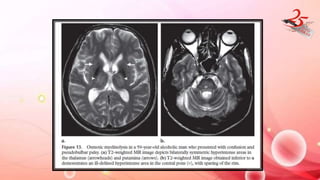

OSMOTIC MYELINOLYSIS

• CAUSE : electrolyte imbalance, chronically alcoholic pts, chronically

debilitated organ transplant pts , rapid overcorrection of

hyponatremia.

• Oligodendroglial cells are more susceptible to osmotic stresses.

IMAGING FINDINGS:

• MRI : T1 and T2 hyperintensity in affected areas

• Central pontine myelinolysis : Symmetric trident shaped / bat wing

shaped T2 /FLAIR hyperintensity in central pons

• Ventrolateral pons and pontine portion of CST are spared

• Extrapontine myelinolysis : T2 hyperintensity in GP , putamen ,

thalamus and cerebellum.

• DWI R in early stages – not typical though

DIAGNOSIS : Imaging + serial Na measurement

OSMOTIC MYELINOLYSIS • CAUSE: electrolyte imbalance, chronically alcoholic pts, chronically debilitated organ transplant pts , rapid overcorrection of hyponatremia. • Oligodendroglial cells are more susceptible to osmotic stresses.

OSMOTIC MYELINOLYSIS IMAGING FINDINGS: •MRI : T1 and T2 hyperintensity in affected areas • Central pontine myelinolysis : Symmetric trident shaped / bat wing shaped T2 /FLAIR hyperintensity in central pons • Ventrolateral pons and pontine portion of CST are spared • Extrapontine myelinolysis : T2 hyperintensity in GP , putamen , thalamus and cerebellum. • DWI R in early stages – not typical though DIAGNOSIS : Imaging + serial Na measurement